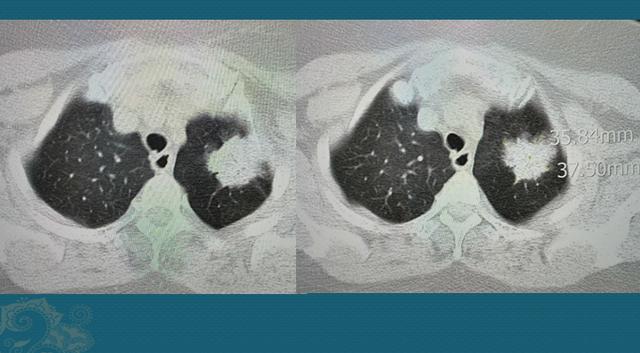

肺癌中期

刘懿博士说肺癌(二亖〇亖)当地医生说中期,我认为是晚期肺癌!

肺癌肿瘤致千疮百孔 精准靶向成功修补

的男病人,抽烟多年,因为咳嗽,痰中带血丝半个月,ct发现右侧中心型肺癌